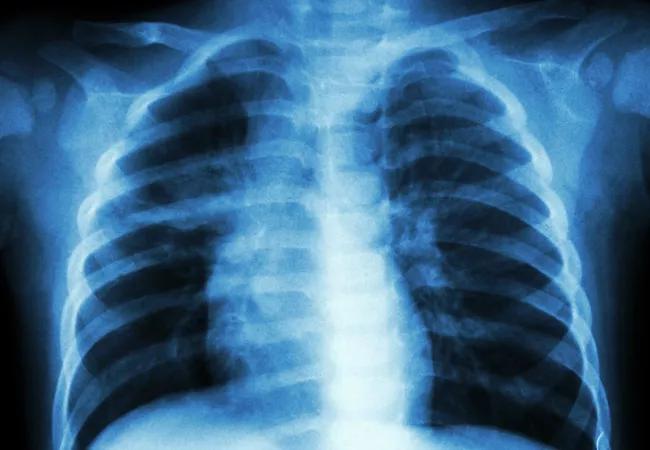

Chest X-ray (CXR) prior to thyroid surgery continues to be routinely obtained at some institutions despite the lack of evidence for its utility. Because unnecessary testing would be adding medical, financial and personal expenses without benefit, physicians at the Cleveland Clinic Endocrinology & Metabolism Institute aimed to determine if obtaining a CXR before thyroidectomy is clinically useful.

The practice of ordering a CXR before surgery originally stemmed in the 1940s when it was done to identify asymptomatic tuberculosis carriers and evolved thereafter to routine pre-operative testing to identify underlying disease and to help in postoperative care. This practice first began to be questioned in the 1970s, and some studies have since been conducted in an attempt to establish proper criteria for testing. To try to determine whether obtaining a CXR impacted perioperative management, we investigated whether difficult intubation or cancer stage correlated with CXR abnormalities.

This study retrospectively looked at 594 consecutive patients who underwent thyroidectomy at Cleveland Clinic from January 2004 to December 2009. Those without a CXR were excluded from the study. Data were collected including demographics, CXR findings, anesthesia records, pathologic data including cancer stage and the presence of metastases. Of the 594 patients, 494 had a pre-operative CXR (Fig.1). Seventy-three percent had cancer on pathology and 16 percent had evidence of distant metastases.

The most common abnormality was rib or other skeletal abnormality, which occurred in 25.3 percent of all chest X-rays, followed by tracheal deviation 16 percent, cardiomegaly 12 percent, lung nodules (6 percent, of which 3 percent were subcentimetric and 0.5 percent showing diffuse nodularity), emphysema 2 percent and pleural effusion 1 percent. Of 78 patients (15.8 percent) with tracheal deviation on CXR, only 5 percent had a difficult intubation during surgery. CXR was shown to impact management in 4 percent, i.e., 100 preoperative CXRs would need to be performed in order to alter the course of management in only four cases.

In assessing for the presence of metastases, it was observed that non-metastatic cancers were more likely to have CXR abnormalities than metastatic cancers. Furthermore, while evaluating the two major CXR abnormalities that would be clinically relevant in patients with malignancy, i.e., the presence of lung nodules and tracheal deviation, there was no significant difference in metastatic versus non-metastatic cancers, meaning that obtaining a CXR was of no added diagnostic benefit.

When deciding to perform any medical procedure, one must weigh the risks versus the benefits to justify the necessity of the procedure. Although obtaining a CXR is a relatively harmless procedure, it does expose patients to a minimal amount of radiation and imposes added cost without an apparent added benefit. Our study showed that obtaining a CXR was not predictive of perioperative complications and the presence of abnormalities did not correlate with increased likelihood of cancer.

We therefore concluded that the utility of preoperative CXR in patients undergoing thyroidectomy, including for thyroid cancer, is very limited. In the climate of value-based care, routine use of this test may be considered redundant and should be ordered only if otherwise clinically indicated.